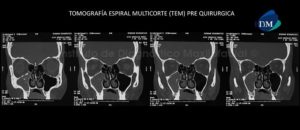

Paciente masculino, 54 años es referido al Instituto de Diagnóstico Maxilofacial para planificación de cirugía guiada con el objetivo de colocar implantes dentales en el